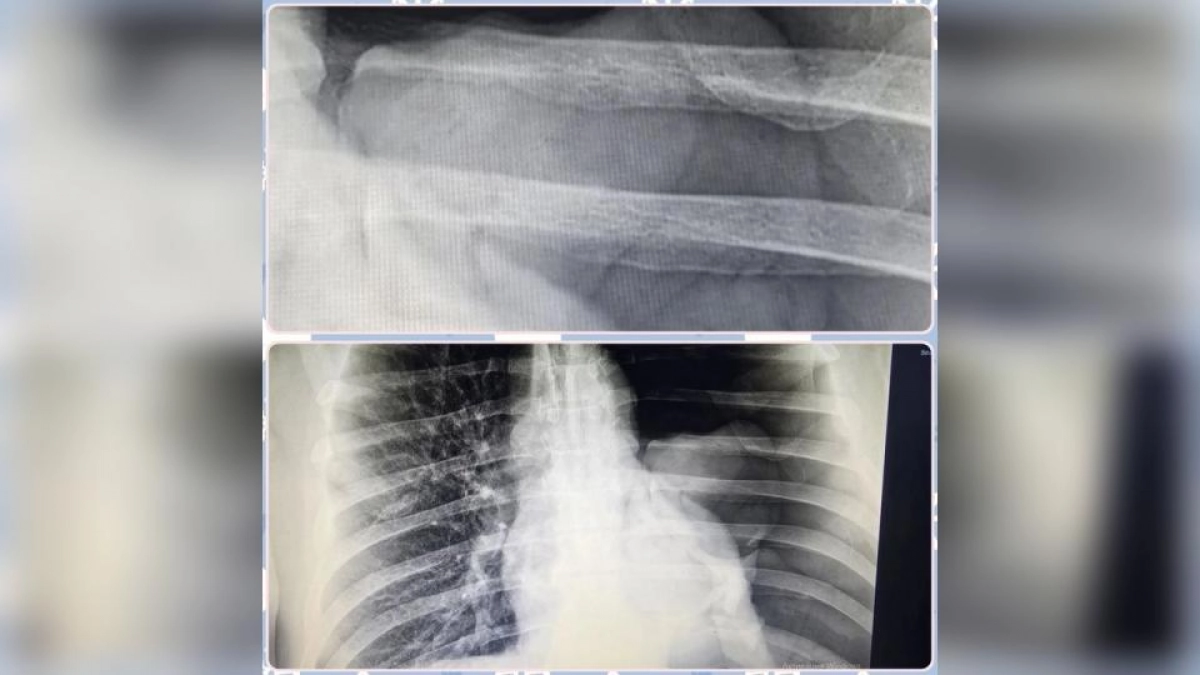

Первым помощь потребовалась 49-летнему жителю села Маянга, который упал с двухметровой высоты. Из-за одышки и болевых ощущений он обратился за медицинской помощью только через три дня. У пациента диагностировали нефункционирующее левое легкое и напряженный пневмоторакс. По словам заведующего травматологическим отделением Алексея Засенцева, состояние удалось стабилизировать посредством экстренного дренирования.

Второй пострадавший, 65-летний местный житель, получил травму во время мытья окон. В результате падения со стремянки у него зафиксировали открытый многооскольчатый перелом голени, сопровождающийся смещением костных отломков. Специалисты выполнили операцию с применением аппарата внешней фиксации, а восстановление пациента займет около восьми месяцев.

Еще один пострадавший, 69-летний мужчина из села Широкий Буерак, получил увечья в гараже. Падение обернулось переломами ребер и рваной раной грудной клетки с отрывом большой грудной мышцы. Пациенту провели операцию под общим наркозом.